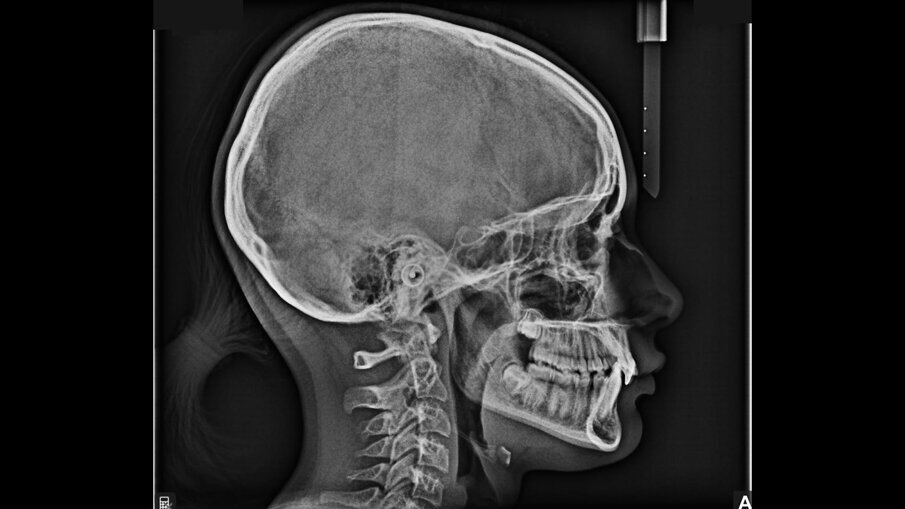

All’esame obiettivo intraorale si riscontra sul piano frontale un severo morso profondo con precontatto traumatico degli incisivi superiori contro la papilla retroincisiva e le rughe palatine anteriori durante la massima intercuspidazione, con overbite di 10 mm (Fig. 5). Dalle foto laterali si evidenzia una malocclusione di Classe II divisione 2 con scissor bite dell’elemento 1.5 (Figg. 6, 7), mentre dalle foto occlusali si rileva un grave affollamento con contrazione di entrambe le arcate maggiore nella zona premolare (Figg. 8, 9). L’analisi di Bolton mostra un eccesso superiore 3-3 di 2,34 mm (73,6%) e 6-6 di 2,76 mm (88,8%). L’analisi cefalometrica evidenzia una Classe II scheletrica, modello facciale normodivergente, angolo interincisale aumentato, incisivi superiori e inferiori retroinclinati (Fig. 10). La radiografia panoramica mostra la presenza dei germi dei terzi molari, assenza di parallelismo tra le radici dei premolari inferiori (Fig. 11) e una sovraeruzione degli incisivi inferiori che crea un doppio piano tra gli incisivi e i molari, segno di una curva di Spee molto profonda.

Fig. 10_Teleradiografia pre-trattamento.